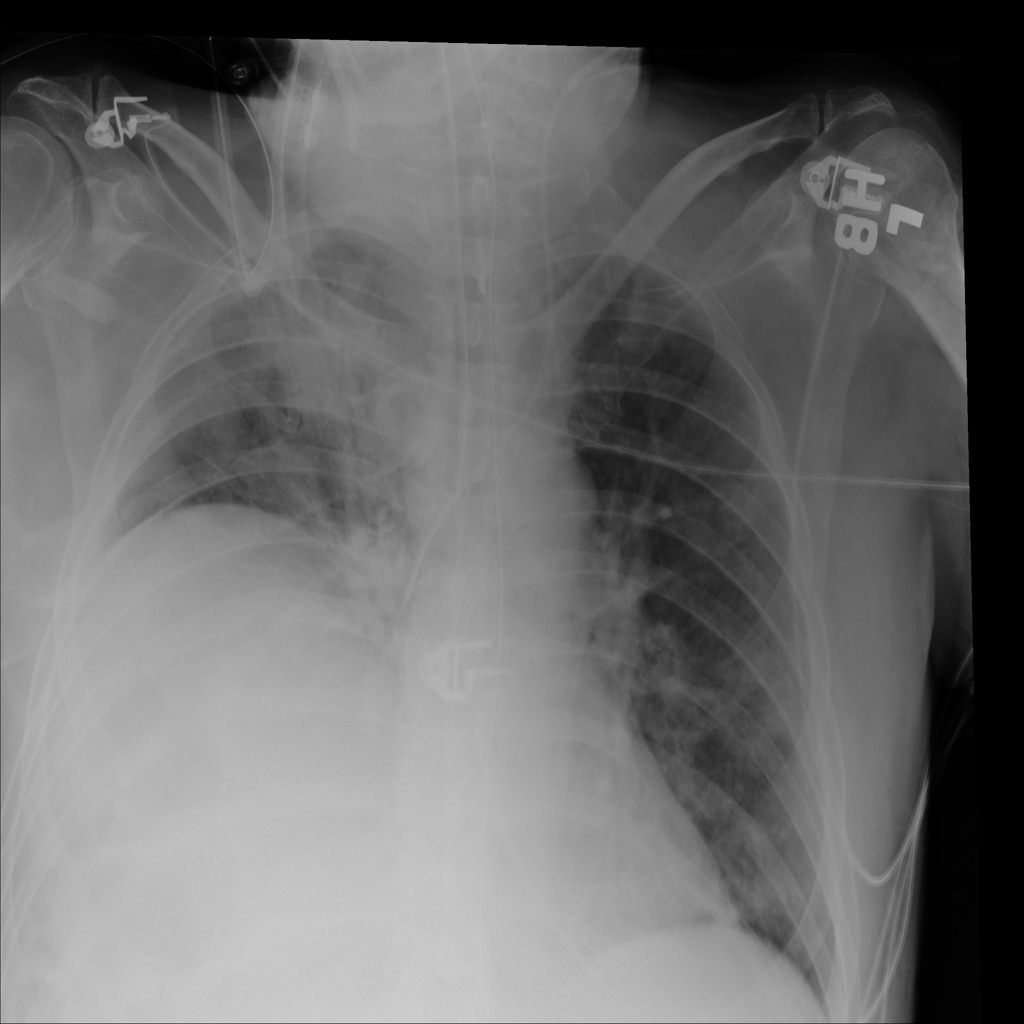

PAT-D7A5 · IMG-000Mass

PAT-D7A5 · IMG-000

PA